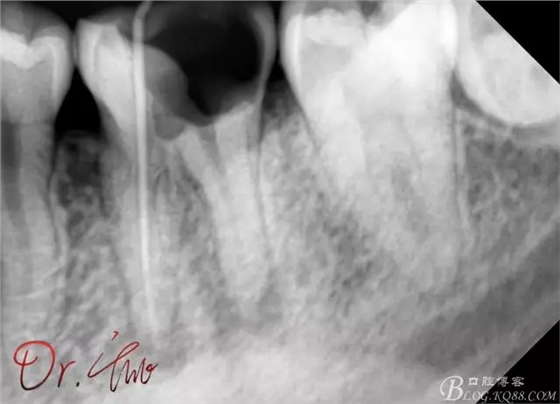

重點第二例病例,初診

拍片確定長度

試主尖,近中頰側(cè)形成臺階

試主尖,近中頰側(cè)再次拍片查看臺階位置及確定長度